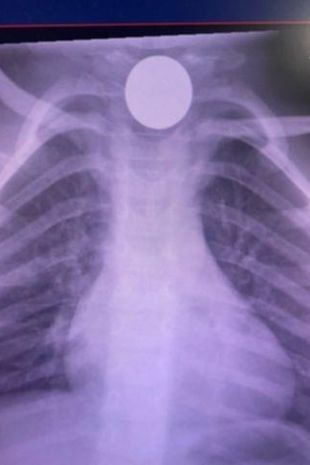

جورجیا سپس چند ضربه به پشت پسرش زد و با فشردن قفسه سینه او تلاش کرد تا رمینگتون را احیاء کند. سپس آنها در حالی که فرزندشان نفس نمیکشید او را بغل کرده و وارد بیمارستان شدند. پزشکان پس از تثبیت وضعیت کودک اقدام به انجام اسکن اشعه ایکس کردند. اسکن گیرکردن یک سکه در گلوی کودک را نشان میداد. این سکه در حالتی کج در مری کودک قرار داشت و رمینگتون تنها از یک روزنه کوچک قادر به نفس کشیدن بود.